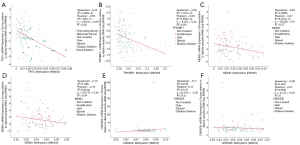

Next, we analyzed the TP53 expression levels specifically in WT. A significant difference existed between the levels of TP53 expression in WT samples and normal samples in the Cutcliffe Renal dataset [P value =0.010, fold change (FC) =1.976]; however, TP53 expression was not significantly different between tumor samples and normal samples in the Yusenko Renal dataset (P value =0.094, FC =1.984) (Figure 2A,B).

Subsequently, we also explored the expression levels of the genes involved in the TP53 signaling pathway. The results showed that MDM2 was significantly overexpressed in the Yusenko Renal dataset (P value =0.05, FC =1.747), but not in the Cutcliffe Renal dataset (P value =0.058, FC =1.955) (Figure 2C,D). The expression levels of MDM4 showed no significant difference in the Yusenko Renal dataset (P value =0.055, FC =1.837) or in the the Cutcliffe Renal dataset (P value =0.501, FC =−1.001) (Figure 2E,F). These results indicated that the TP53 signaling pathway genes are differentially expressed in WT and, therefore, may serve an important role in the tumorigenesis and prognosis of WT.